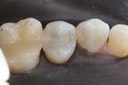

Scott Kanamori #29 prep

Scott Kanamori #29 finish